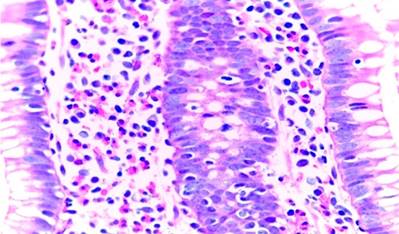

The treating clinicians decided to start the search for the gastrointestinal etiology of eosinophilia associated with gastrointestinal symptoms presented by the patient. First, he underwent an endoscopy in which moderate erythematous gastritis (histopathological examination: mild superficial chronic gastritis, without Helicobacter pylori, atrophy, or intestinal metaplasia) and nonspecific duodenitis (histopathological examination: mild chronic duodenitis with intraepithelial lymphocytes 8-10/100 epithelial cells, without typical findings of a specific disease) were found. Then, he underwent a colonoscopy that presented the following findings: in the distal ileum, from approximately 15 cm from the ileocecal valve to the distal, marked mucosa congestion was observed with “punched” erosions, punctate erythema, and loss of mucosal vascularization (Figure 1). On histopathological examination, moderate chronic ileitis was found with no specific findings. In the cecum, at the level of the ileocecal valve and proximal to the appendicular orifice, erythema of the mucosa and partial loss of mucosal vascularization were observed (Figure 2). There was a significant increase in eosinophils at the level of the lamina propria and crypts, which reached approximately > 200 eosinophils in a high-power field in the histopathological examination (Figures 3 and 4). This eosinophilic infiltrate was also accompanied by plasma cells, scarce lymphocytes, and cryptic abscesses, which are findings related to eosinophilic colitis.

As already described above, a biopsy is essential. Nevertheless, eosinophils represent a normal component of inflammatory cells in the colon. Only they can vary in number in different colon segments, as they can also be part of the inflammatory infiltrate in various colon diseases.17 Eosinophilic density is usually estimated semiquantitatively and requires counting the number of eosinophils by high-power fields (HPF) and the mean count. This density is not yet clearly established to determine the diagnosis of eosinophilic colitis. However, some options have been proposed, such as more than 60 (or even 100) eosinophils/HPF, usually observed in the cecum18,19 or more than 40 eosinophils/HPF in at least two different segments of the colon.6 The finding was more than 200 eosinophils/HPF in our case. The other findings that can be found in histology are mentioned in Table 3.